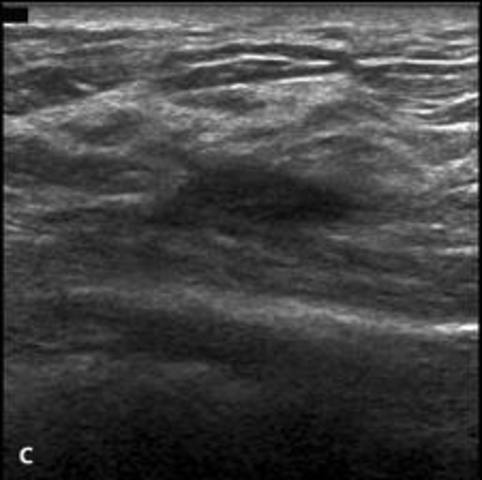

• Breast Elastography

Breast Elastography

Elastography is a new tool that became available over the last decade. Many manufacturers incorporate this feature into their ultrasound systems. Elastography is based on tissue characteristics such as stiffness to create images. Stiffness varies with different types of tissue. Firstly, B-mode image of the mass is obtained. Then compression is applied to the area of interest, and two images are compared side to side.

• Breast Elastography Cont.

Breast Elastography Cont.

ElastographyMachine will make a comparison of the mass' stiffness and its surroundg area and will color code an elastogram accordingly. Colors used to charachterize the tissue are yellow, red, green and blue. Yellow means tumor has low stiffness, blue means it is hard compared to its surroundings.

Here is how it works: Reference: